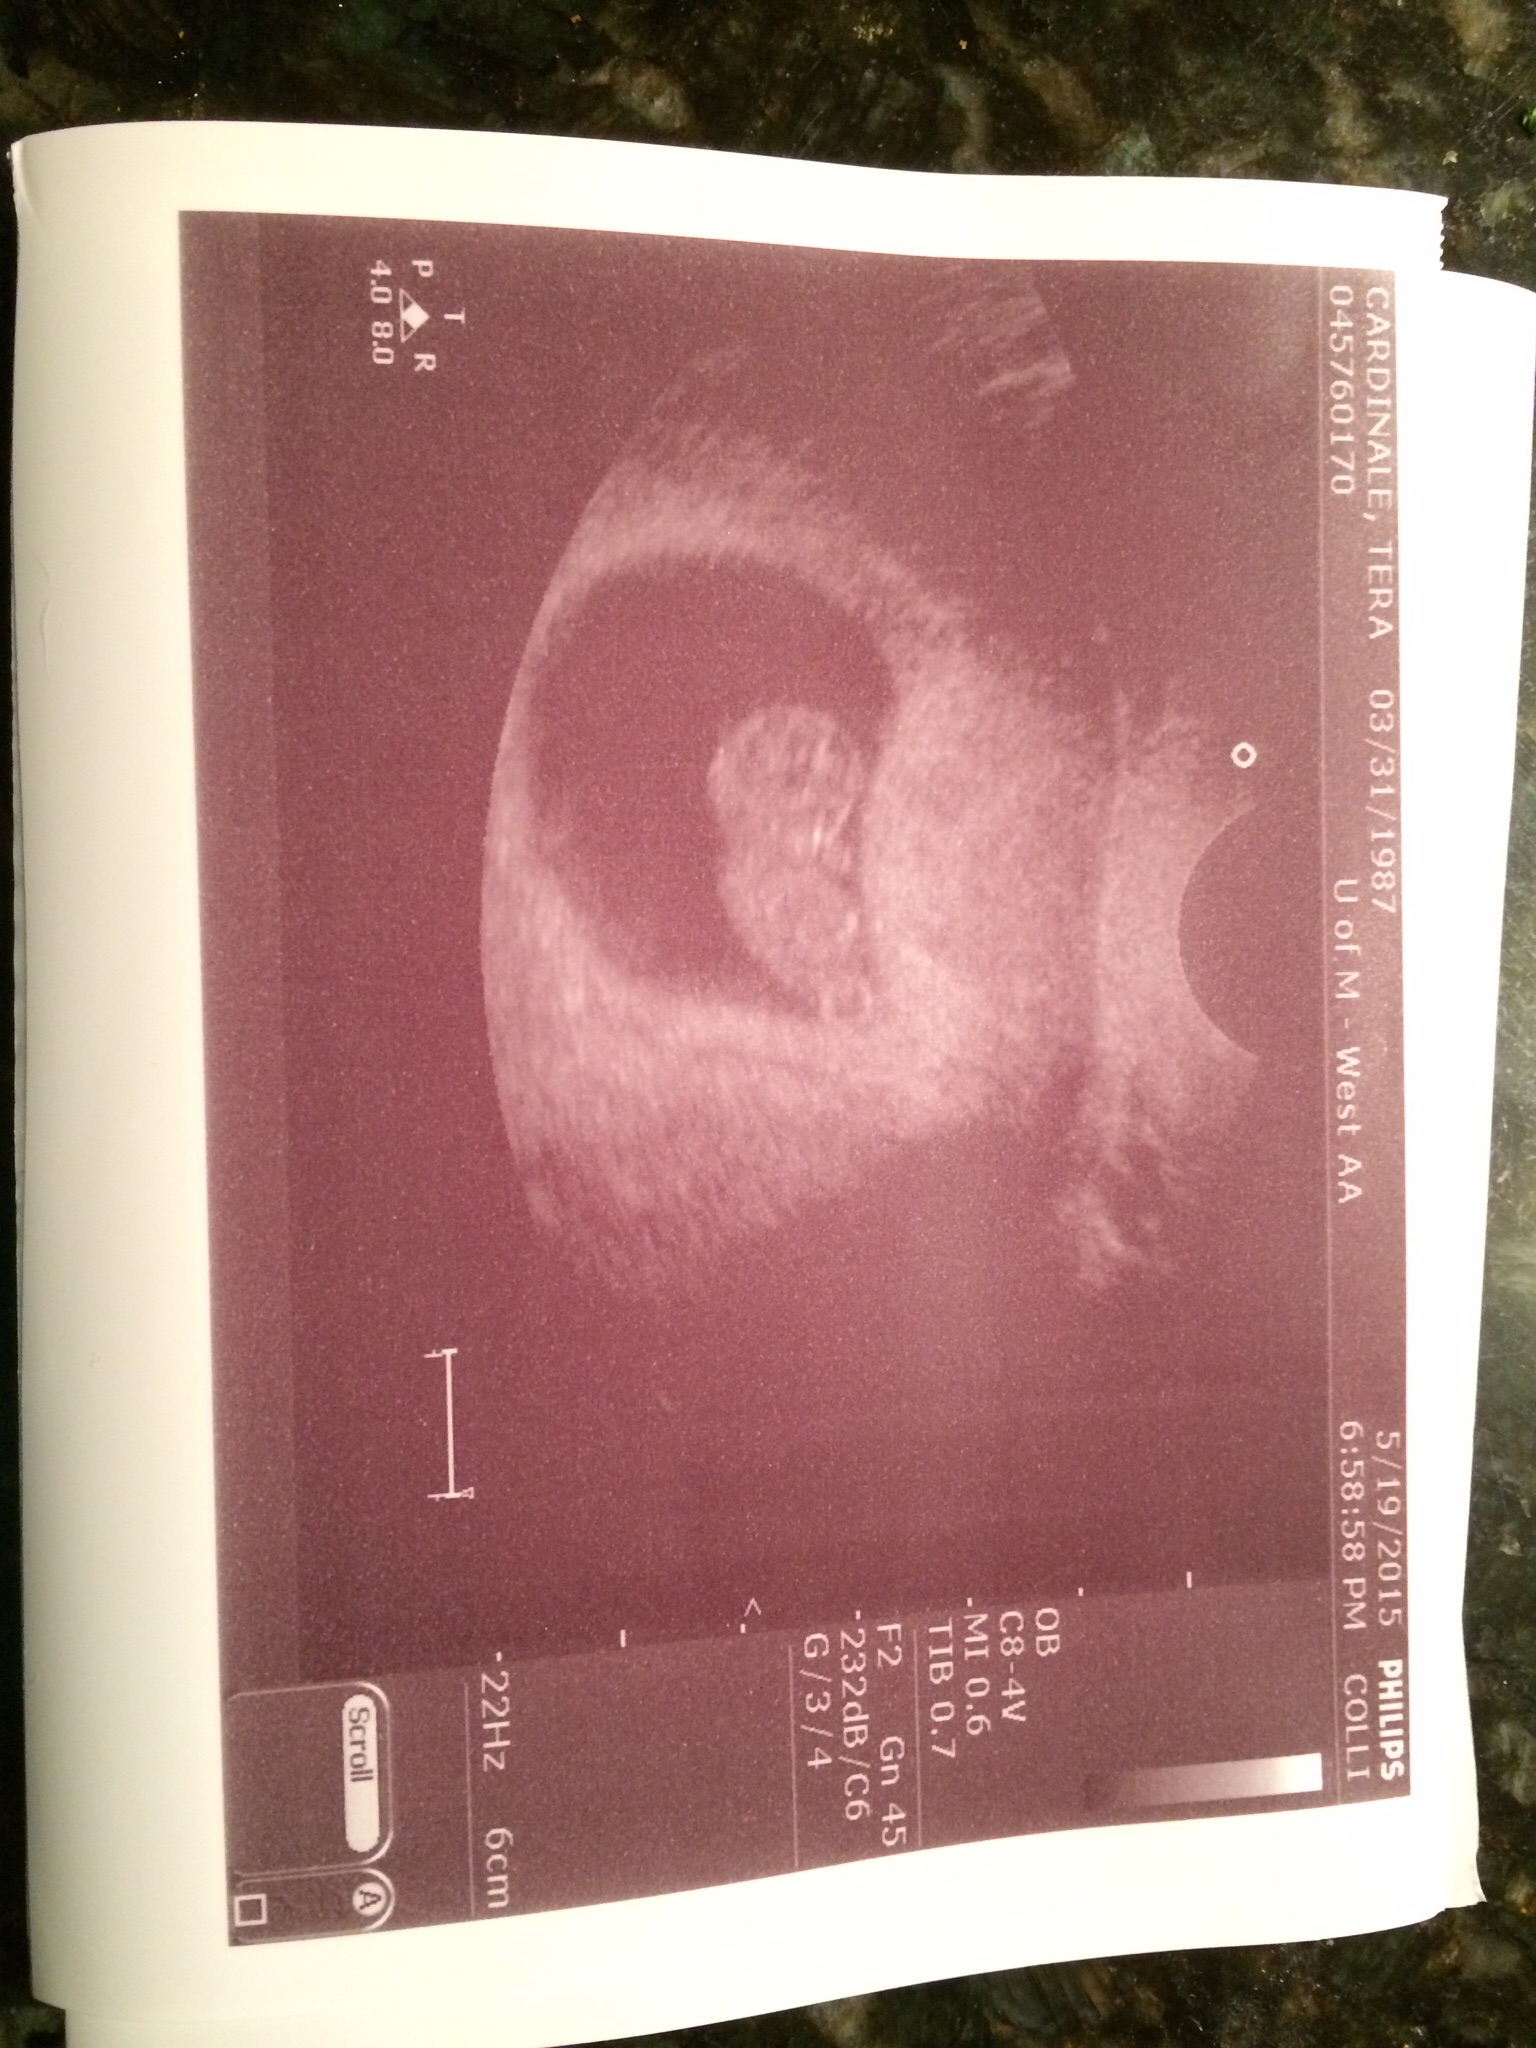

U/S is somewhat hard to see but head on left and arm bud sticking up, waving hi :-h Hi buddy!

Edit: oops, sideways pic confusion